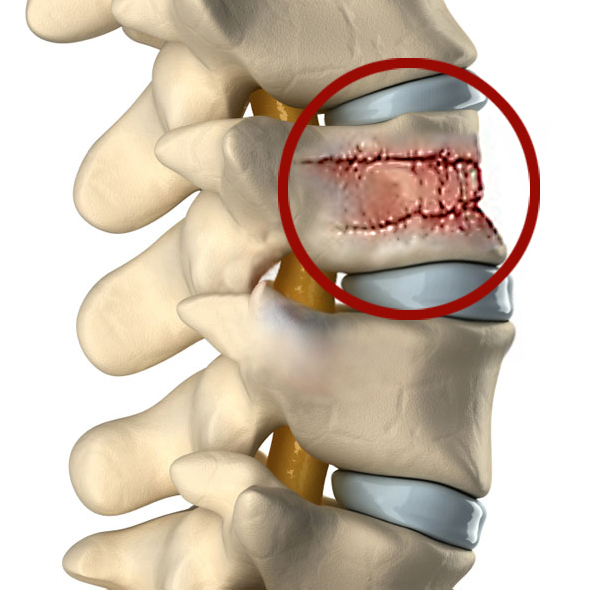

Рентгеновские снимки и медицинские изображения компрессионных переломов